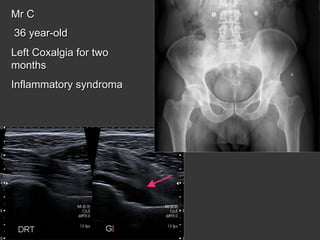

Mr C

36 year-old

Left Coxalgia for two

months

Inflammatory syndroma

bilateral sacroiliitis